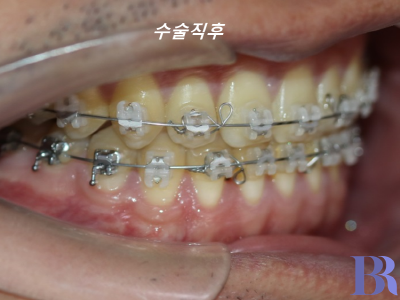

1년정도의 술전교정을 마친 후

수술직후 모습입니다.

수술 직후 치아 모습입니다

반대교합이 잘 해소가 되었네요

교합도 안정적으로 맞물립니다.

교합도 아주 긴밀하게

수술이 잘되었습니다